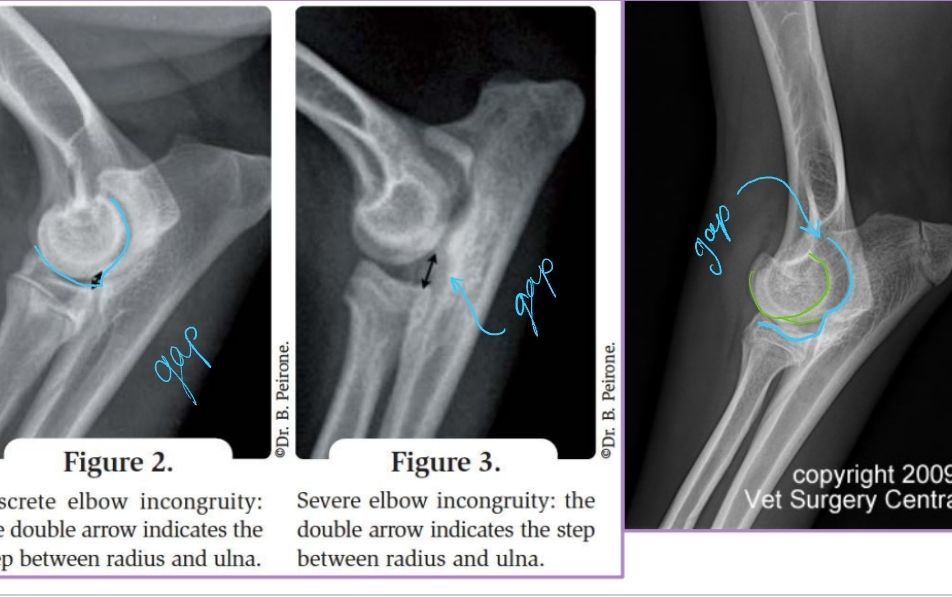

Medial Compartment and Coronoid Disease

Growing/developmental disease, Bilateral

Et: Growth incongruency radius/ulna, abnormal joint stress, pressure on medial coronoid of ulna

Sig: Large breed dogs, Labs, Bernese Mountain Dog, Male > Female, 6-18 months

Cs: OA, Lameness with ambulation, Decreased ROM of elbow joint, Pain(PE/palpation), Minimal joint effusion, Muscle atrophy

Dt: Lateral, AP, flexed, Crlat-oblique

Rads: Osteophytes(back of elbow), Effusion, Subtrochlear sclerosis, Joint incongruity

CT: Most sensitive

Elbow Incongruity

Et: Asynchronous growth of radius and ulna

Dt: radiographs